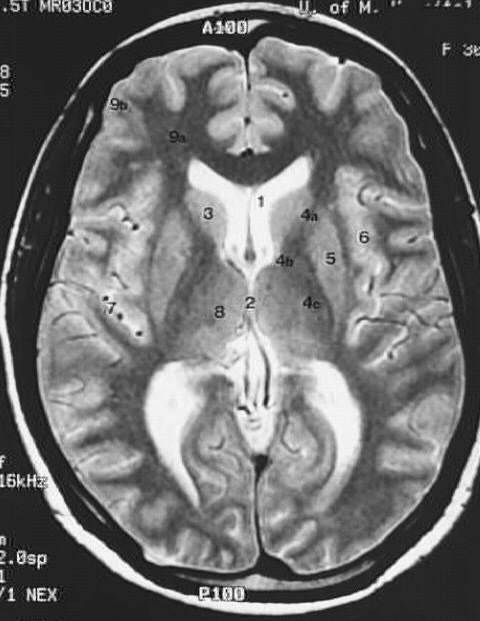

Head & Neck: Head MRI Internal Capsules:

1. Lateral ventricle

2. Third ventricle

3. Caudate nucleus

4. a. Anterior limb of internal capsule

b. Genu of internal capsule

c. Posterior limb of internal capsule

5. Lentiform nucleus

6. Insula

7. Insular artery

8. Thalamus

9. a. White matter

b. Gray matter